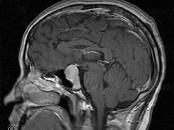

问题 男,41岁,头昏伴头痛1年,请根据所提供图像,选择最可能的诊断()

选项 A.(鞍区)脑膜瘤 B.(鞍区)颅咽管瘤 C.(鞍区)生殖细胞瘤 D.(鞍区)转移瘤 E.(鞍区)垂体腺瘤

答案 E